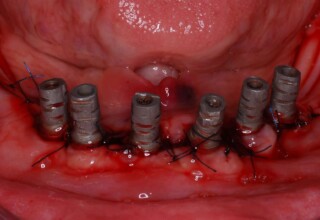

Κάτω γνάθος: εξαγωγές, άμεση τοποθέτηση εμφυτευμάτων και άμεση φόρτιση(την ίδια ημέρα) με προσωρινή γέφυρα

Άνω γνάθος: σταδιακές εξαγωγές, σταδιακή τοποθέτηση εμφυτευμάτων και σταδιακή ενσωμάτωση τους στην προσωρινή γέφυρα ώστε η ασθενής να μην μείνει ούτε μια ημέρα χωρίς αποκατάσταση. Στόχος η συνεχής λειτουργική και αισθητική αποκατάσταση της ασθενούς χωρίς άμεση φόρτιση των εμφυτευμάτων λόγω ανατομικών ιδιαιτεροτήτων.

Χρησιμοποιήθηκαν παλαιές χαμογελαστές φωτογραφίες της ασθενούς γιατί είχε χαθεί τελείως το φυσικό σχήμα των δοντιών εξαιτίας των πολλαπλών προσθετικών προσπαθειών που είχαν γίνει στο παρελθόν. Μεταφέρθηκε στην προσωρινή γέφυρα η σχέση των φυσικών δοντιών μεταξύ τους άλλα και με τα χείλη. Δοκιμάστηκε η φώνηση και η μάσηση με δυο διαφορετικές προσωρινές άνω γέφυρες και εκτιμήθηκε η αισθητική απόδοση τους. Αφού επιτεύχθηκαν σε βαθμό ικανοποιητικό η φώνηση και η αισθητική εμφάνιση της οδοντοφυΐας, η προσωρινή αποκατάσταση χρησιμοποιήθηκε ως οδηγός για την τελική.